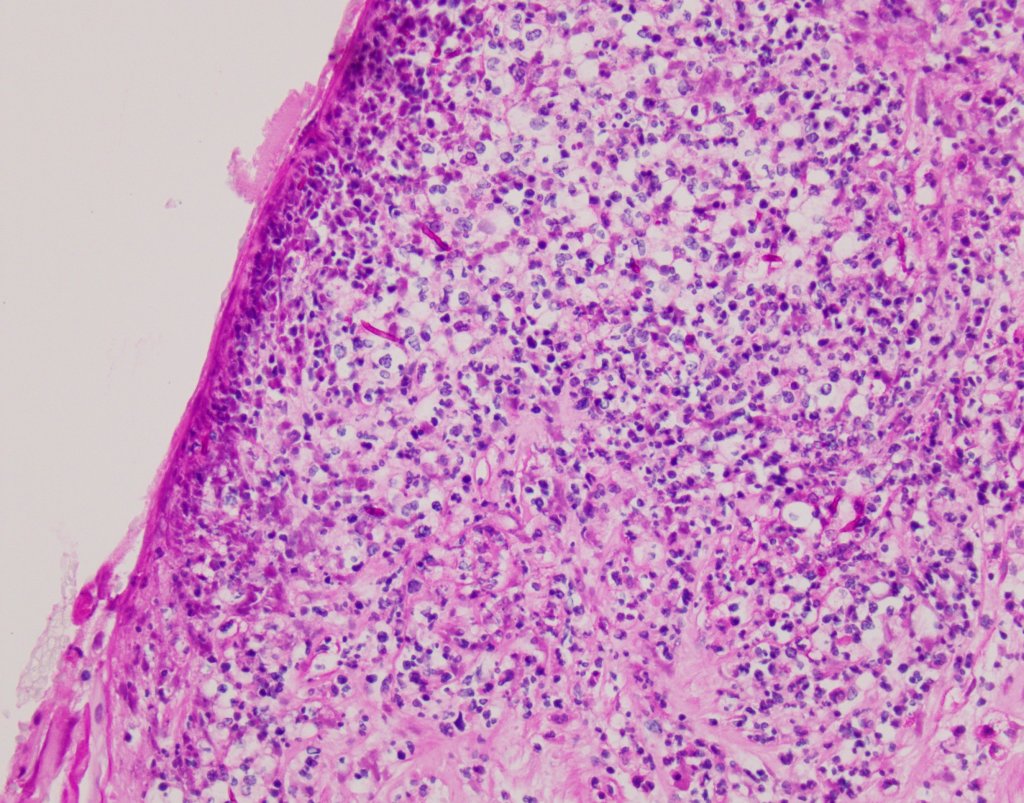

- Microscopically: the most common finding is inflammation of the umbilical cord (funisitis). Funisitis represents fetal response and may involve only umbilical vein or all three blood vessels with the spillage into Wharton’s jelly. If the acute information is reaching the surface of the umbilical cord, one should think about candida infection and perform special stains to highlight potential fungal microorganisms. Many times grossly described white lesions may correspond with squamous metaplasia of the amniotic epithelium.